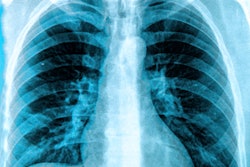

A three-minute artificial intelligence (AI)-based chest x-ray test that might speed up emergency department triage of suspected COVID-19 patients with respiratory symptoms has been created by Bering Limited.

A new AI algorithm gave an accurate COVID-19 result in a test environment in under three minutes, with performance on par with four certified radiologists, according to an article published recently in Scientific Reports.